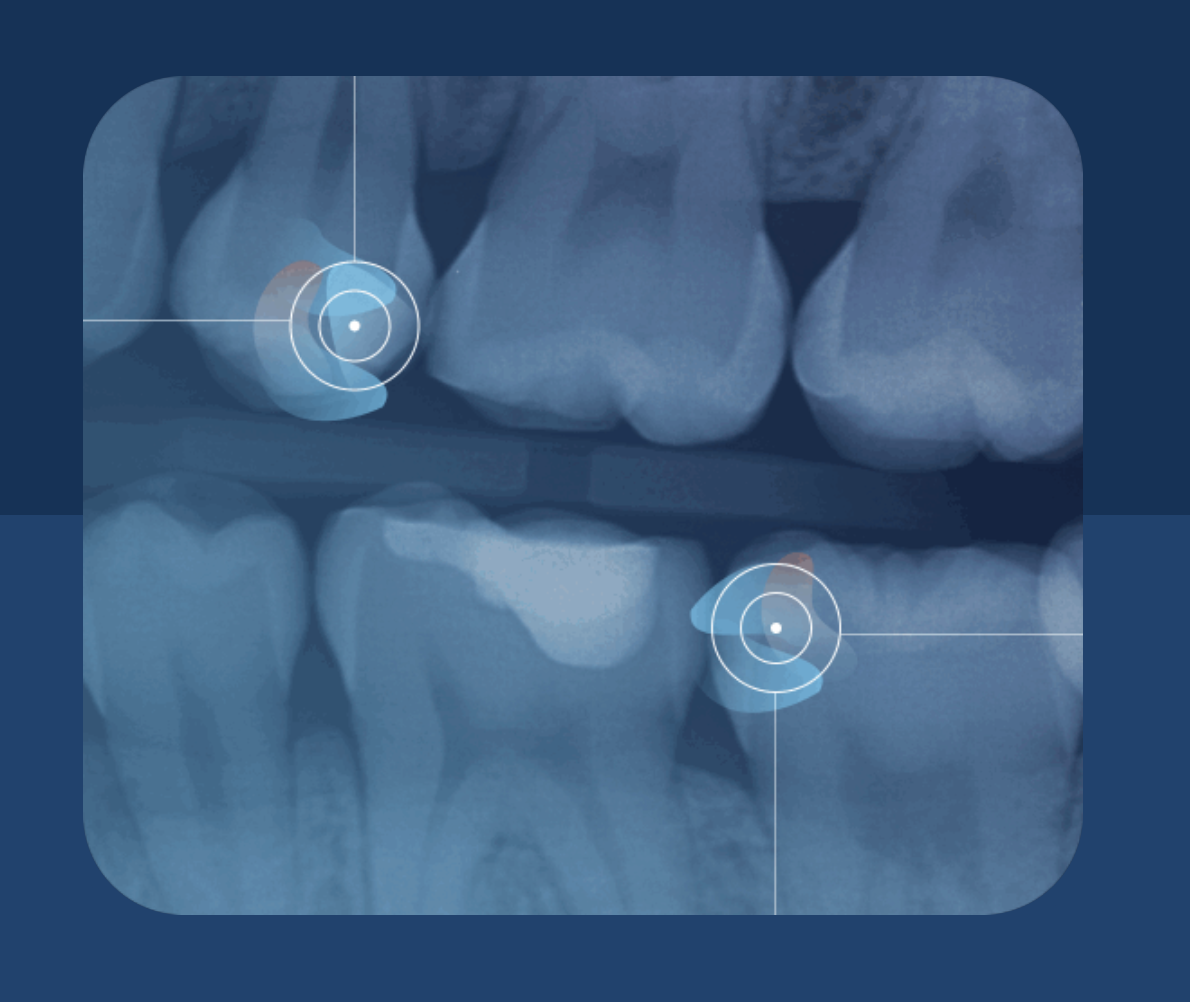

Second Opinion®

A smarter way to review your dental X-rays — for better clarity and confidence.

At Nordonia Dental, we’re committed to giving you the most accurate, thorough care possible. That’s why we use Second Opinion®, an advanced AI technology that helps our team review dental X-rays with an added layer of support.

Think of it as a “second set of eyes” that highlights areas we may want to take a closer look at — so we can catch issues early, explain findings clearly, and help you make confident decisions about your care.

Second Opinion® is an FDA-cleared AI-assisted technology that reviews dental X-rays in real time and helps identify signs of common dental conditions.

It does not diagnose or replace your dentist — it simply provides additional insight so our doctors can deliver the most accurate evaluation possible.

Second Opinion® can highlight signs of many common conditions,

including:

• Cavities

• Bone loss

• Calculus

• Infections and inflammation around the root

• Impacted teeth

• Signs of failing dental work

• Widened periodontal ligament